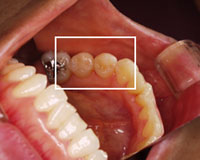

接着技術により、何度も同じ部分が虫歯になる状態を改善した患者さまの症例

治療前

他医院にて虫歯部分を削り、金属の詰め物をしていた部分の金属をはずしている状態 。.

虫歯治療による2次齲触(虫歯治療した部分に再度バイキンが入り込み、また虫歯になっている状態)